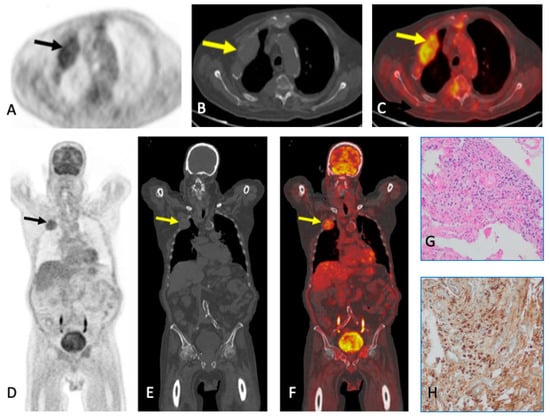

6. Plasmacytoma and Extramedullary MM

- Salaun, P.-Y.; Gastinne, T.; Frampas, E.; Bodet-Milin, C.; Moreau, P.; Bodere-Kraeber, F. FDG-Positron-Emission Tomography for Staging and Therapeutic Assessment in Patients with Plasmacytoma. Haematologica 2008, 93, 1269–1271. [Google Scholar] [CrossRef] [PubMed]

- Fouquet, G.; Guidez, S.; Herbaux, C.; Van De Wyngaert, Z.; Bonnet, S.; Beauvais, D.; Demarquette, H.; Adib, S.; Hivert, B.; Wemeau, M.; et al. Impact of Initial FDG-PET/CT and Serum-Free Light Chain on Transformation of Conventionally Defined Solitary Plasmacytoma to Multiple Myeloma. Clin. Cancer Res. 2014, 20, 3254–3260. [Google Scholar] [CrossRef] [PubMed]

- Galán González, I.; Santos Salas, X.; Campos Rivas, R.; Idoate Ortueta, C.; Muñoz Olmedo, J.M.; Gómez León, N.N. Comparación Entre La RM y La 18FDG PET/TC En El Diagnóstico de Los Plasmocitomas Con Correlación Anatomo Patológica. Seram 2018. Available online: https://www.piper.espacio-seram.com/index.php/seram/article/view/2921 (accessed on 30 August 2023).

- Hall, M.N.; Jagannathan, J.P.; Ramaiya, N.H.; Shinagare, A.B.; Van Den Abbeele, A.D. Imaging of Extraosseous Myeloma: CT, PET/CT, and MRI Features. Am. J. Roentgenol. 2010, 195, 1057–1065. [Google Scholar] [CrossRef]